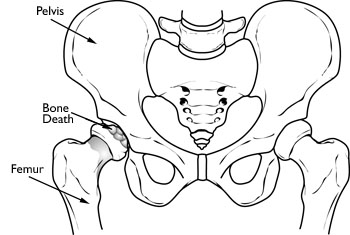

With osteonecrosis, the bone in the head of the femur slowly dies.

Osteonecrosis can progress from a normal, healthy hip (Stage I) to the collapse of the femoral head (Stage IV).

Osteonecrosis of the hip develops when the blood supply to the femoral head is disrupted. Without adequate nourishment, the bone in the head of the femur dies and gradually collapses. As a result, the articular cartilage covering the hip bones also collapses, leading to disabling arthritis.